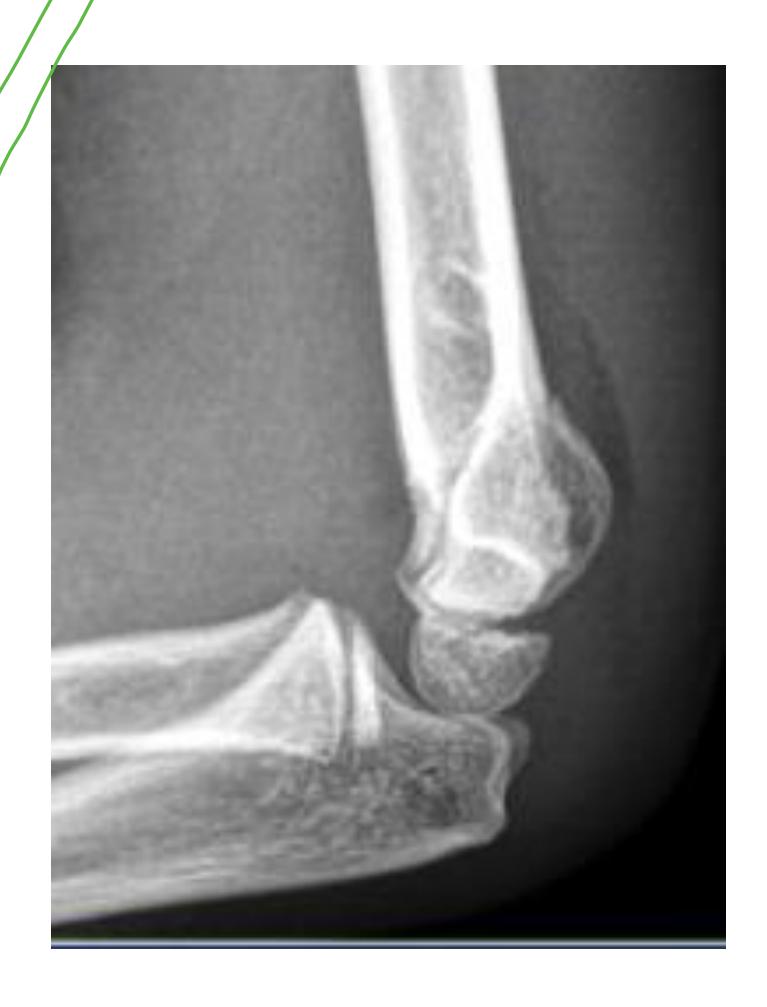

Supracondylar Fractures

Clinical Presentation

- What is the characteristic finding in supracondylar fractures? Supracondylar fracture in children with fat pad sign

Treatment Protocol

- What are the treatment options for supracondylar fractures?

- If not displaced: Back slab above elbow (flexed elbow)

- If displaced: Closed reduction and fixation with K-wires and slab

Emergency Room Management: Back slab with flexion in 30 degrees and send for AP and L x-rays

Radial Head Dislocation

Clinical Diagnosis

- How is radial head dislocation diagnosed?

Possible dislocation of the head of radius

- Draw a line from the neck of the radius - it wonโt pass through the capitellum center